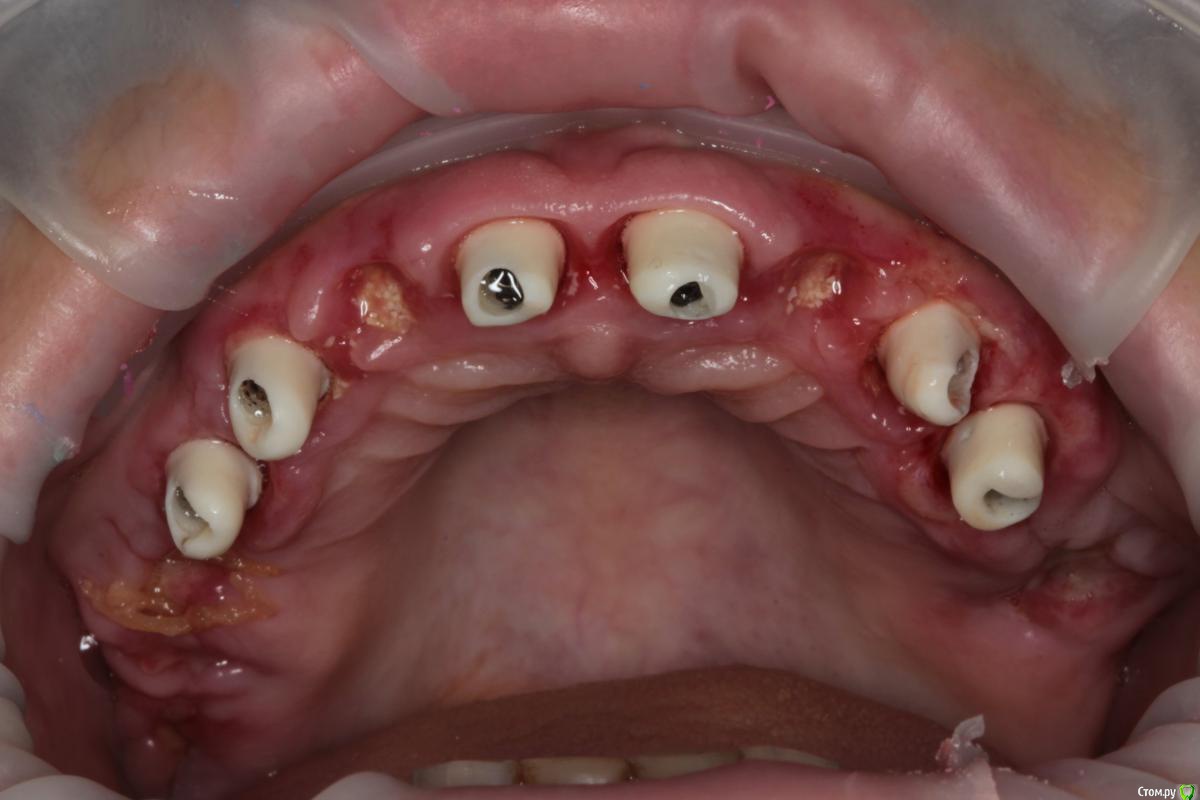

Популярный пост Abuk Опубликовано 24 ноября, 2015 Популярный пост Поделиться Опубликовано 24 ноября, 2015 Планировали 8 имплантатов.Буду рад конструктивной критике.Фото с мокап.Через 6 днейДалее хотели поставить 6 ки, она отказалась (не хотели синусы)и решили все по-другому .Через 2мес пришла с отколотыми консолями )Прошу прощения ,что ортопедию выложил не в том разделе), не хотел делить. 26 1 Ссылка на комментарий

Abuk Опубликовано 24 ноября, 2015 Автор Поделиться Опубликовано 24 ноября, 2015 (изменено) Радикально Вы. Что оставили ей после имплантации-это инд аббатменты? На них мокап одели и нагрузили сразу? У всех был торк хороший? Или это временные абб? Что за систему использовали? В планах консоль назад, правильно я понимаю?Спасибо.увидев такую работу,сам так же подумал бы). Но там подвижность 2-3 ст. ближе к 3. Мосты болтались ,2 ки в хлам. 1 ки только стабильны. Снимал мосты,проводил кюретаж. Решил дернуть.Абатманы временные, тех. сделал на них коронки. Система анкилоз. Работа,на посл. фото, постоянная . Имплы в области 4 и по одному моляру ,консоли. Мок ап был до имплантации . По нему шаблон. Стабильность 15 -20 на 23 , остальное больше 30. Изменено 24 ноября, 2015 пользователем Abuk 1 Ссылка на комментарий